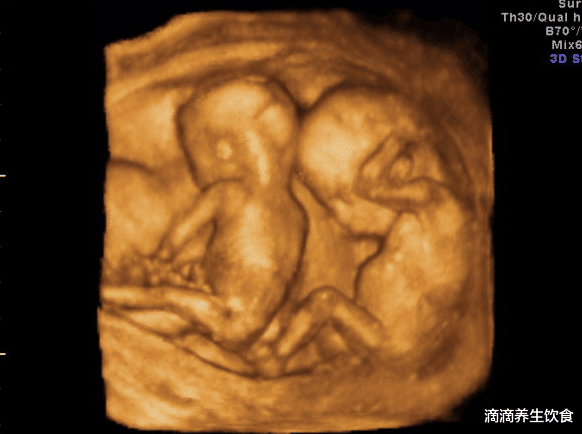

周先生今年28岁 , 是一名白领 , 周先生的父母因为年纪大了 , 两个老人的心愿就是希望能抱上孙子 , 于是两个老人从老家搬来到城里和周先生两口子一起住 。 1年前 , 周老太太不知从哪里听来的消息 , 说是村里有一对夫妻 , 保持半年不同房 , “养精蓄锐” , 最后怀了一对双胞胎 , 可把周老太太羡慕坏了 。 二话不说就让儿子和媳妇分房睡 , 说是自己也要抱双胞胎孙子 。